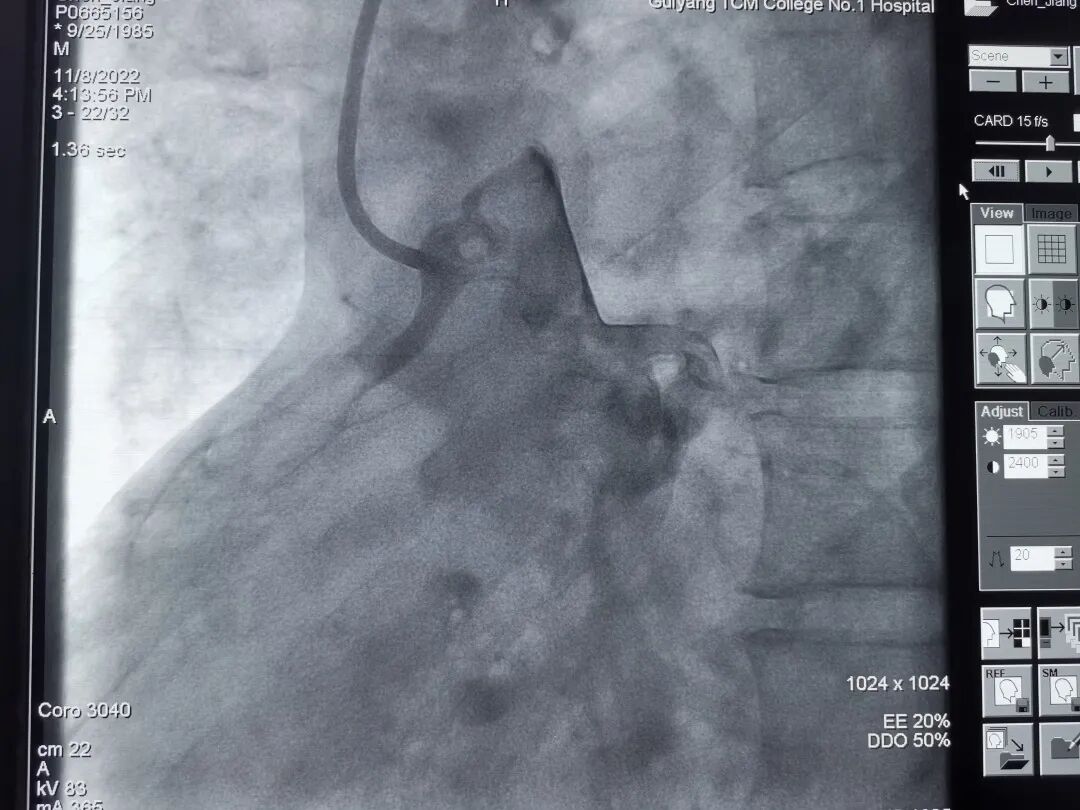

118日,在介入室的配合下,由郑涛副主任医师主刀,郭英普主治医师和封挺约主治医师为助手,为患者开展冠脉介入手术。术中选择了右侧股动脉路径,尝试多次后JR造影管终于找到右冠脉开口,造影显示右冠开口在升主动脉后壁并高于左冠开口,为极少见的冠脉变异开口,同时造影显示右冠近段以远完全闭塞,前向血流TIMI 0级。

造影导丝是什么再克技术堡垒  巧破闭塞病变——心血管内科应用平行导丝技术救治冠脉慢性完全闭塞患者!_https://www.jmylbn.com_新闻资讯_第5张

右冠脉造影显示右冠开口变异伴右冠完全闭塞